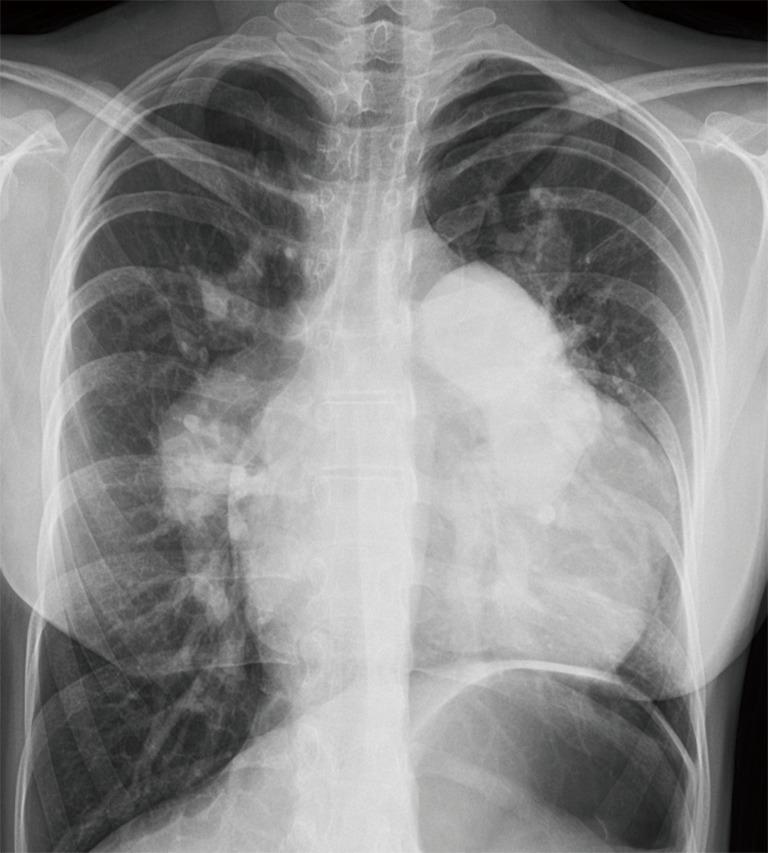

Thanks to advances in pediatric cardiology, most infants with tetralogy of Fallot (TOF) now survive into adulthood. This relatively new population of adult patients may face long-term complications, including pulmonary regurgitation (PR), right ventricular (RV) tract obstruction, residual shunts, RV dysfunction, and arrythmias. They will often need to undergo pulmonary valve (PV) replacement and other invasive re-interventions. However, the optimal timing for these procedures is challenging, largely due to the complexity of evaluating RV volume and function. The options for the follow-up of these patients have rapidly evolved from an angiography-based approach to the surge of advanced imaging techniques, mainly echocardiography, cardiac magnetic resonance (CMR), and computer tomography (CT). In this review, we outline the indications, strengths and limitations of these modalities in the adult TOF population.